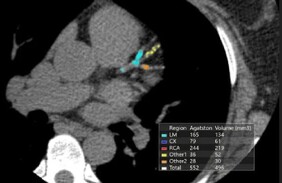

CT calcium score

A calcium score helps with your decision regarding decide the need for treatment to prevent a heart attack or stroke. This investigation is most helpful for people who do not have a clear high or low risk but somewhere in the middle. A calcium score is quick and non-invasive.

Many people are offered statin therapy but are unsure as to whether they should take this medication fearing side effects. A calcium score allows patients to make a more informed decision regarding use of these medications moving forward.

If you have no symptoms and are concerned about your risk of heart attack or stroke this is the preferred investigation.